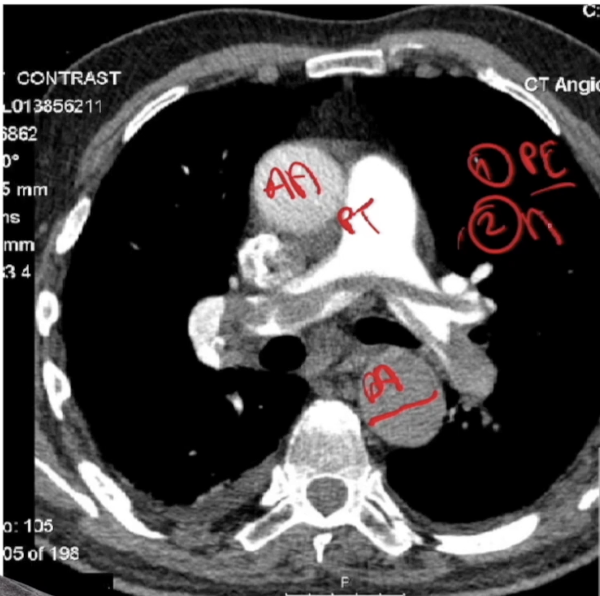

imaging

imaging- concern for/

saddle embolism

false lumen- Aortic Dissection